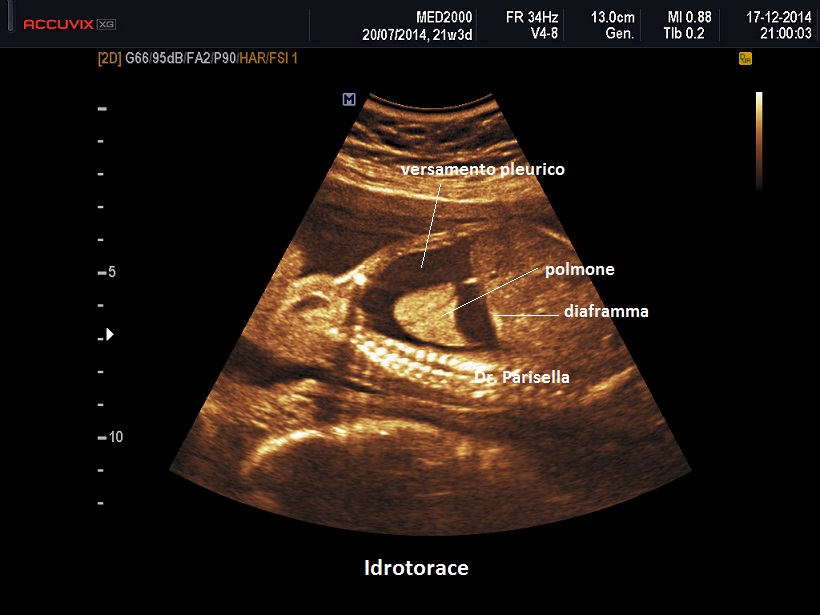

Diagnosi Ecografica

La diagnosi ecografica non offre in genere difficoltà ed è rappresentata da un versamento pleurico monolaterale o bilaterale.

Nelle forme monolaterali si ha shift mediastinico con dislocazione controlaterale del cuore.